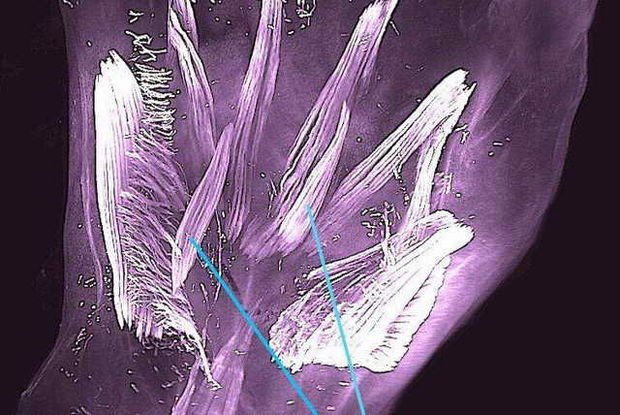

Elm adamları hamiləliyin yeddinci həftəsində insan dölünün qollarında və ayaqlarında 30 əzələnin olduğunu, bunların üçdə birinin 13 həftədən sonra yox olduğu və ya bir-biri ilə birləşdiyini söyləyir.

Yalnız fetal inkişaf zamanı yaranan qarın əzələlərindən bəzilərinin izahı verilə bilmir. Bundan əlavə, atavizmlərin embrionun 11.5 həftəlik dövründə rudimentar strukturlarının görünməsi də qeyri-adidir.

"Dorsometacarpales” kimi müvəqqəti əzələlər 250 milyon il əvvəl sinapsid sürünənlərin məməlilərə keçidindən bəri insan əcdadlarının təkamülünü əks etdirir. Ancaq nadir hallarda bunlar böyüklərdə də müşahidə olunur. Belə anomaliyaların səbəbi anadangəlmə pozğunluqlar ola bilər.